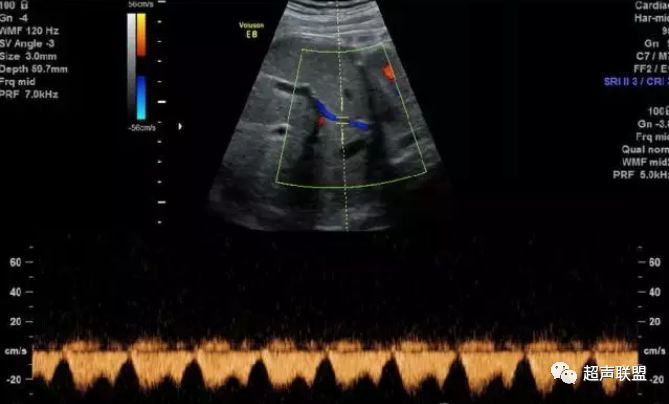

图4 大脑中动脉血流阻力减低